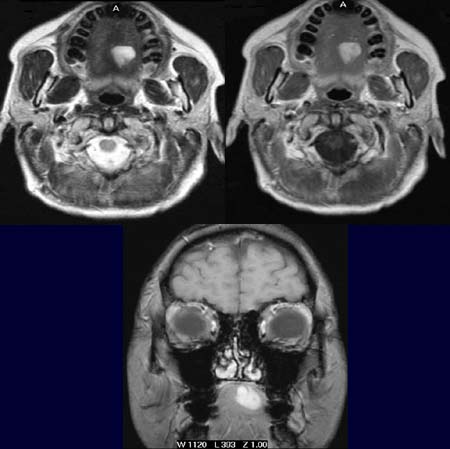

In

der T2-Wichtung (linkes Bild oben) kommt im Mundboden links eine signalreiche

Raumforderung zur Darstellung. In T1-Wichtung vor Kontrastmittelgabe

ohne Fettunterdrückung (rechtes Bild oben) ist die Raumforderung

ebenfalls signalreich.

Nach Kontrastmittelgabe in der T1-Wichtung im coronaren Schnitt (unteres

Bild) bleibt die Raumforderung signalreich.